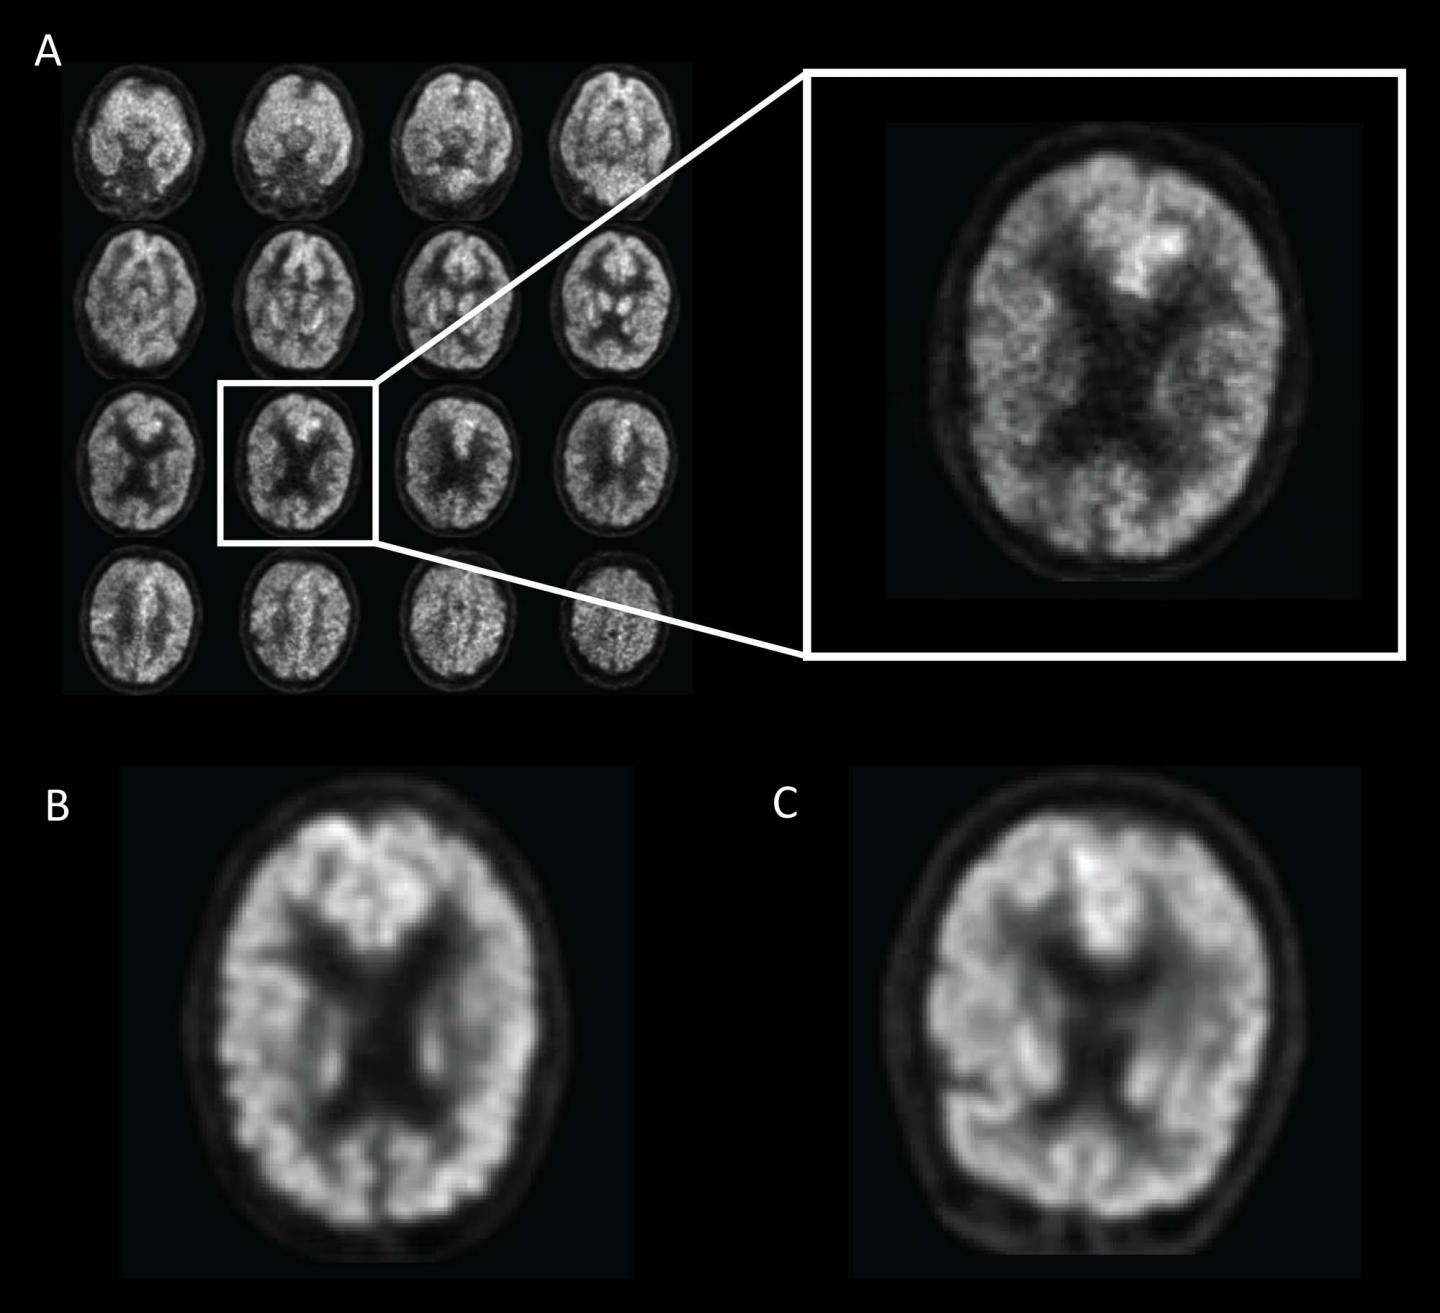

The researchers trained the deep learning algorithm on a special imaging technology known as 18-F-fluorodeoxyglucose positron emission tomography (FDG-PET). In an FDG-PET scan, FDG, a radioactive glucose compound, is injected into the blood. PET scans can then measure the uptake of FDG in brain cells, an indicator of metabolic activity.

The researchers had access to data from the Alzheimer's Disease Neuroimaging Initiative (ADNI), a major multi-site study focused on clinical trials to improve prevention and treatment of this disease. The ADNI dataset included more than 2,100 FDG-PET brain images from 1,002 patients. Researchers trained the deep learning algorithm on 90 percent of the dataset and then tested it on the remaining 10 percent of the dataset. Through deep learning, the algorithm was able to teach itself metabolic patterns that corresponded to Alzheimer's disease.

Finally, the researchers tested the algorithm on an independent set of 40 imaging exams from 40 patients that it had never studied. The algorithm achieved 100 percent sensitivity at detecting the disease an average of more than six years prior to the final diagnosis.